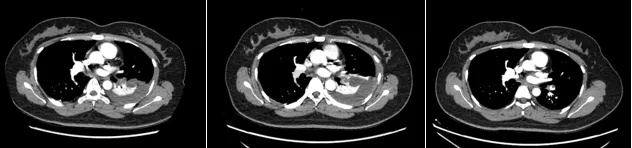

患者影像检查变化

经过规范的溶栓、抗凝治疗,患者咳嗽及咳嗽时胸痛的情况明显好转,复查造影结果显示,肺梗死灶和胸腔积液均有明显改善。